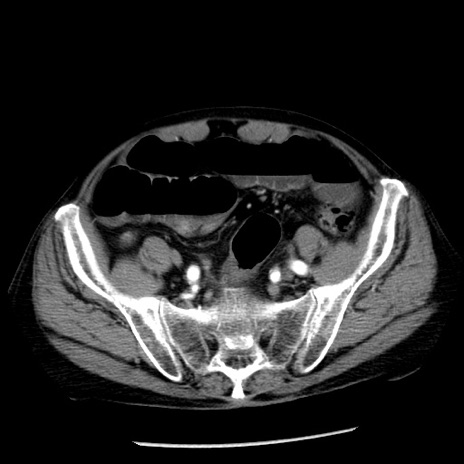

症例26(横断像)

【症例】80歳代男性

【主訴】嘔吐

【現病歴】昨晩2回嘔吐あり、今朝になっても嘔吐あり。来院。

【既往歴】胃潰瘍

【身体所見】意識清明、BT 37.6℃、BP 166/95mmHg、HR 100bpm、SpO2 97%、腹部:平坦・軟、腸蠕動音聴取良好、圧痛なし。

【データ】WBC 21900、CRP 1.46